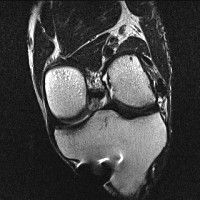

무릎 mri 간단히 봐주실 수 있으시나요 ㅠㅠ

안녕하세요 8년전 십자인대 수술하고 최근 무리한 운동에 무릎 불편감이 생겨서

mri 찍었습니다.

진단결과는 첫 찍은 병원에서 활액막염 이라는 진단을 받았습니다. 혹시 봐주실 수 있으실까요?

올라온 MRI가 단편적이라서 정확한 진단에 어려움이 있지만 십자인대에는 큰 이상이 있지는 않은것 같으며, 무릎관절내 물이 있는 것으로 보아 활액막염의 진단이 맞을 것 같습니다.

하지만 단편적인 영상이기 때문에 촬영병원에서 정확한 판독지 등을 받으시는 것이 좋겠습니다.